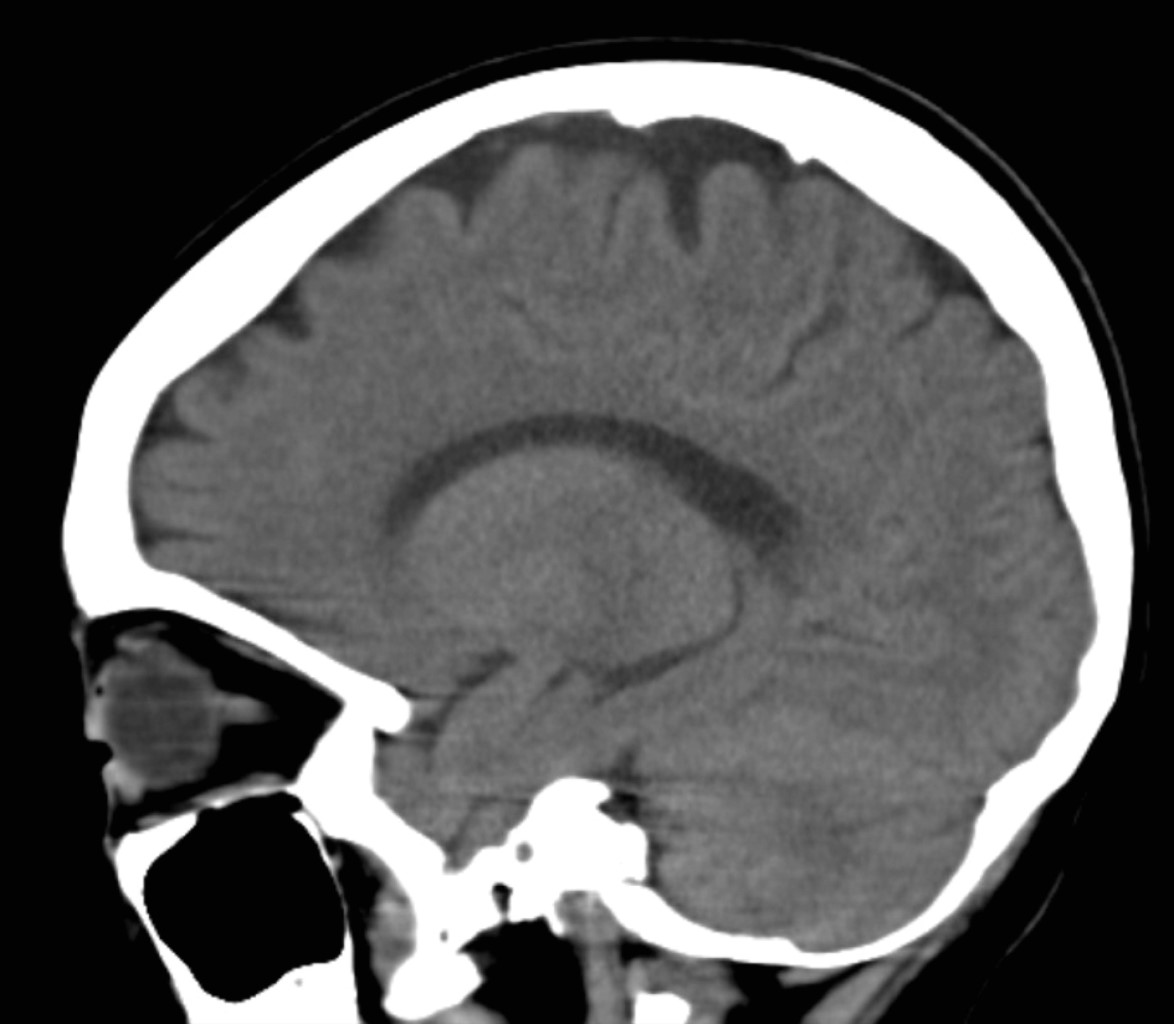

El análisis del electrocardiograma evidencia taquicardia sinusal sin otra alteración. Radiografía de tórax sin lesiones. Ante la sospecha de trombosis arterial se solicita ultrasonido Doppler de emergencia que reporta trombosis venosa profunda y superficial de miembro pélvico izquierdo, arteria iliaca externa permeable, arteria poplítea izquierda presentando flujo en su interior, no audible y sin espectro Doppler (Figura 2). Se realiza angiotomografía contrastada que evidencia edema de tejidos blandos, disminución del calibre de arteria femoral del lado izquierdo en tercio medio y distal, sin paso de contraste a partir de la arteria poplítea, trombosis venosa superficial y profunda en extremidad izquierda, extremidad derecha sin alteraciones (Figura 3). Tomografía de cráneo sin evidencia de patología (Figura 4). Inicia manejo con anticoagulación (enoxaparina), pentoxifilina, terapia hídrica con soporte con aminas vasoactivas (adrenalina y dobutamina) y antibiótico de amplio espectro (ceftriaxona), además de transfusión de hemoderivados e ingreso a Unidad de Terapia Intensiva Pediátrica.